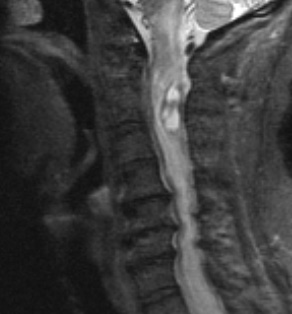

Case 1 History ---- The patient is a 67 year old woman with myopathy. ---- MRI revealed C1 to C3 intramedullary vascular tumor: 1A1 STIR (Short Tau Inversion Recovery) images are highly water-sensitive and show a variegated pattern in the tumor.